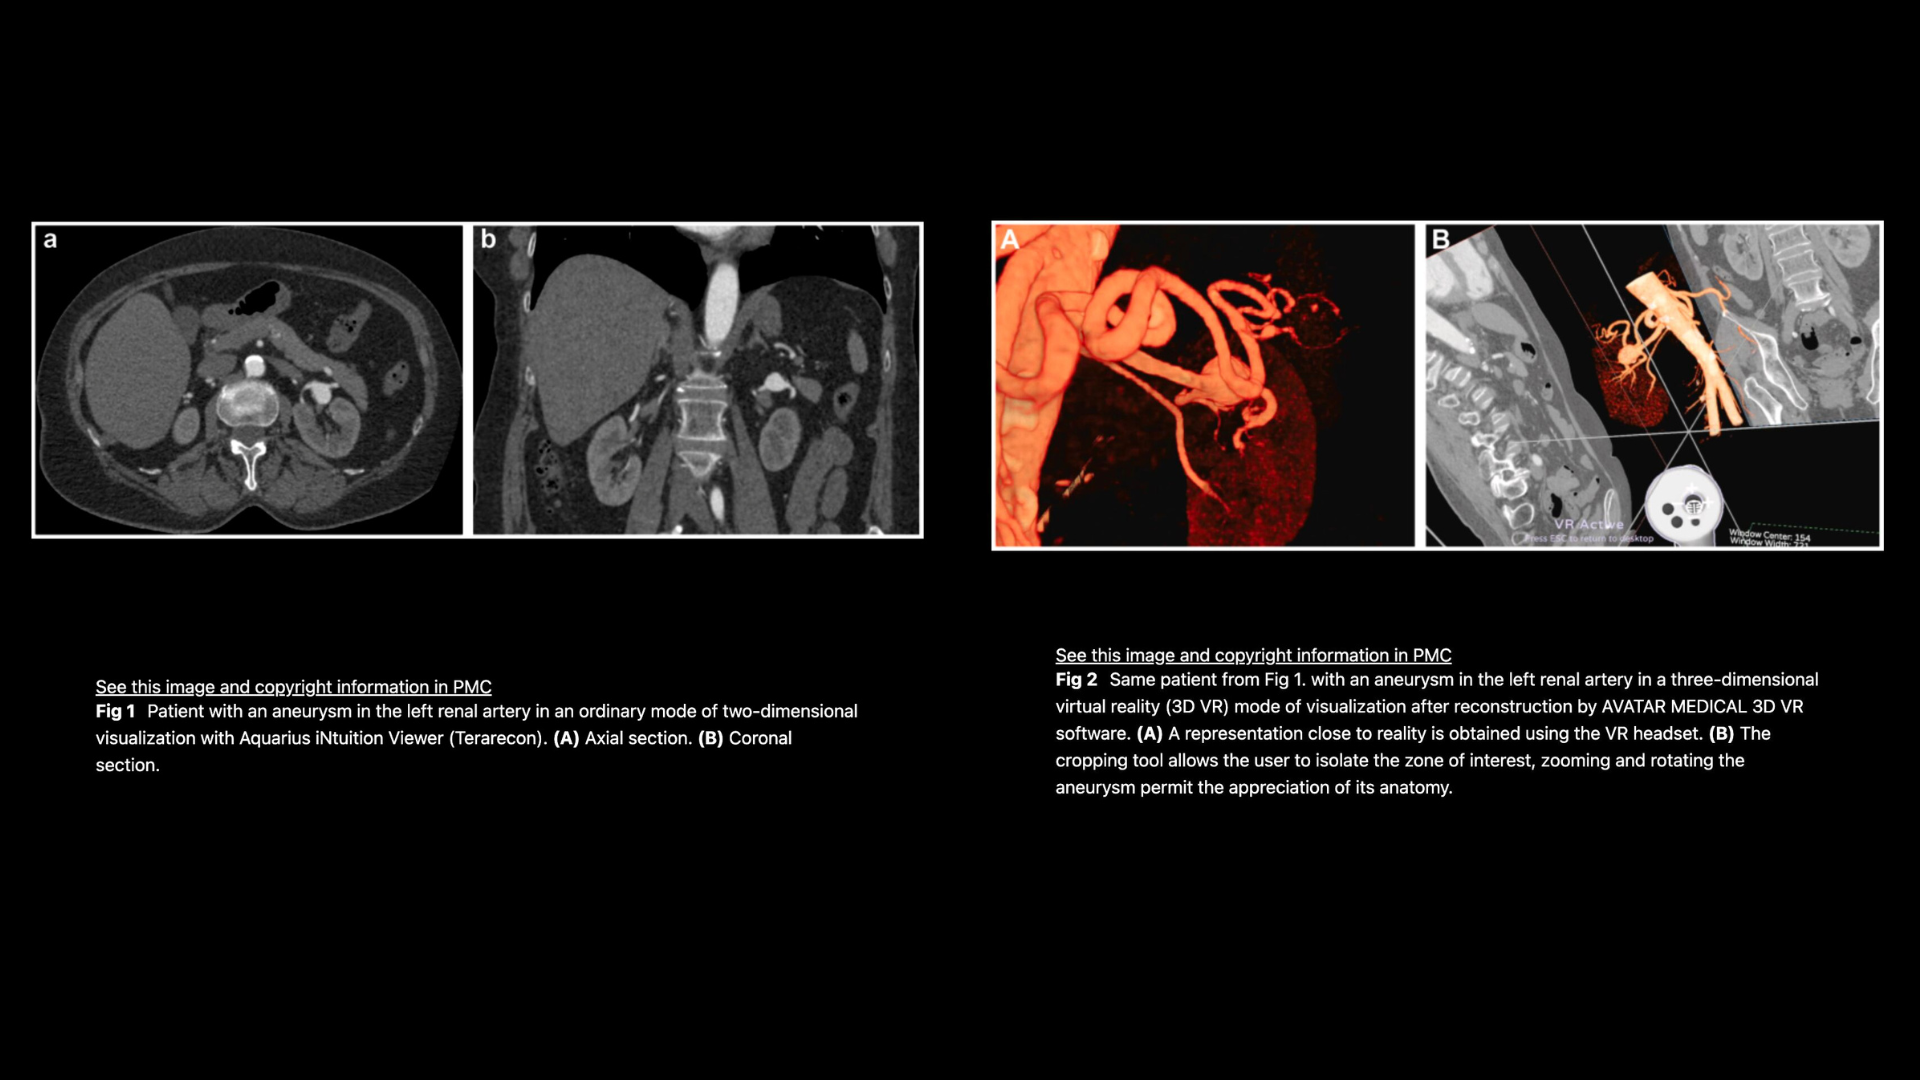

This pilot study assessed the role of 3D virtual reality (VR) analysis in surgical planning for visceral artery aneurysms. Using Avatar Medical Vision, surgeons reported improved anatomical understanding, procedural planning, and anticipation of challenges, with VR influencing the choice between open and endovascular repair in 15% of cases. The findings suggest that VR is a practical, time-efficient tool that can support optimized treatment selection in VAA surgery.